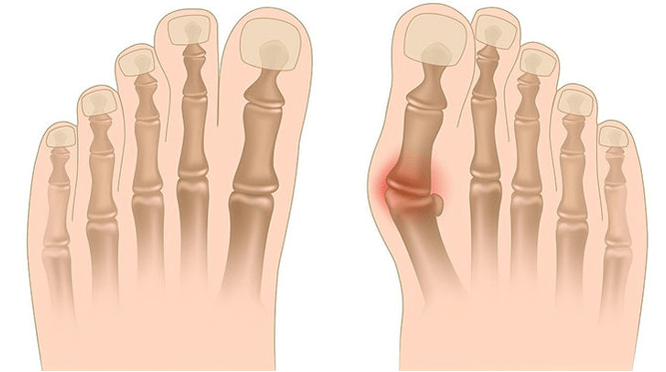

Die Valgus -Deformation ist die Krümmung des Fußes, die durch die Abflachung seines Längsbogens gekennzeichnet ist. Typischerweise wird die innere Kante des Fußes abgesenkt („Tropfen“), und die Ferse stellt sich heraus.

Wenn Sie die Füße nehmen (wenn Sie sie von hinten ansehen), wird auf Knöchelebene eine x-ähnliche Verformung gebildet: Die Knöchel sind in Kontakt, während die Fersen in einer Entfernung von 5 bis 6 Zentimetern voneinander entfernt sind.

In der dritten Stufe wird der Vorsprung des aufgetauten Knochens bestimmt (merklich niedriger als der Knöchel auf der inneren Oberfläche des Knöchels) sowie eine starke Umleitung der Ferse im Freien (der Patient steht auf der inneren Kante des Fersenknochens).

Die fortgeschrittene Valgusdeformation der Füße ist durch eine ausgeprägte Krümmung des Fußes selbst und des Knöchelgelenks gekennzeichnet. Die Patienten beklagen sich über brennende Schmerzen in den Muskeln des Unterbeins sowie über eine erhebliche Gangverletzung: Die Knie reiben sich gegeneinander, während sich der rechte und linke Fuß in einiger Entfernung befindet.